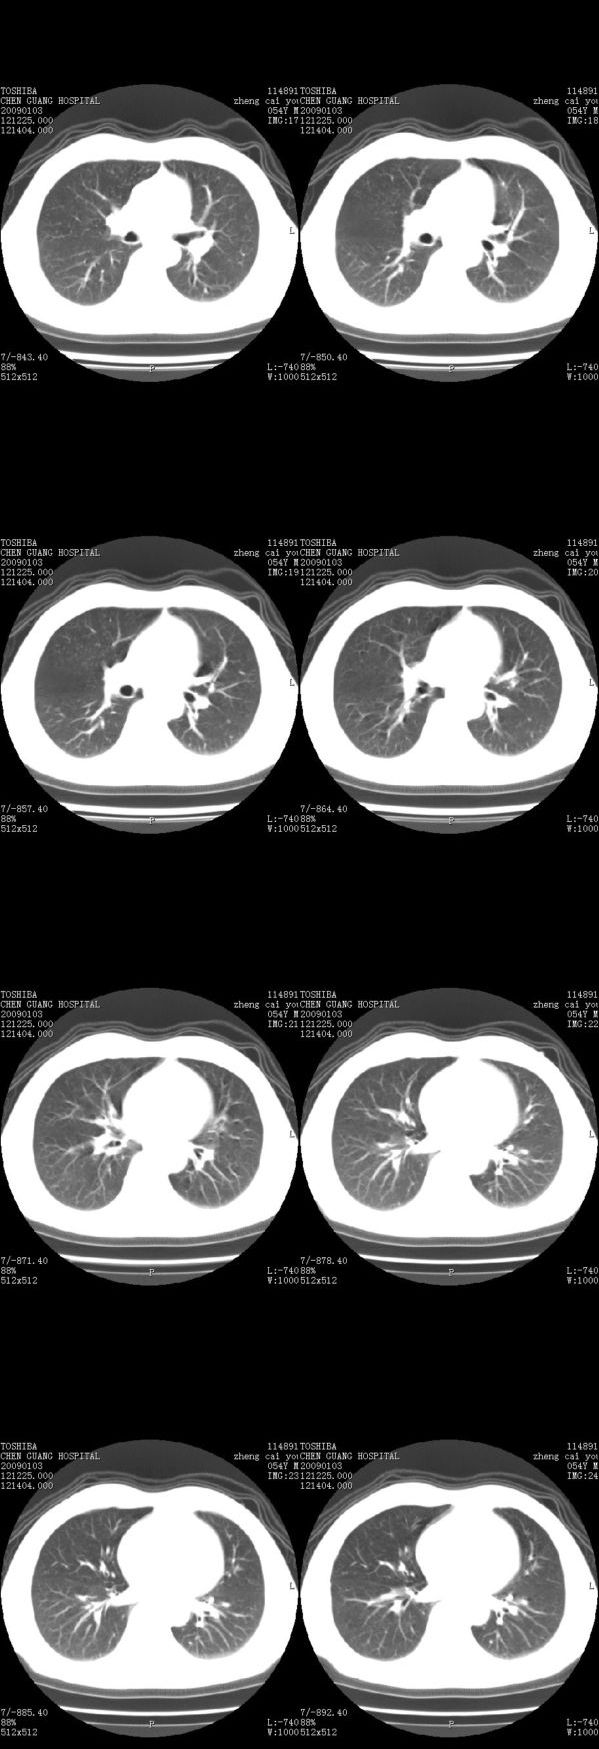

男,54岁,平时有吸烟后咳嗽、咯痰史,因右侧胸部(腋窝下)疼痛来检查平片,见右下肺动脉干起始处处结节,后到同学处做了平扫及增强。请各位老师帮忙看一下,不甚感谢!!!!!

支气管壁增厚

右肺下叶支气管扩张。

顺序确实有点乱,不过在右肺上叶后段近气管旁仍可见一结节灶,希望楼主小心观察分析。

考虑------支气管壁增厚---局限性气肿---建议----气管镜进一步检查

小叶中心型肺气肿

增强了 但纵隔窗调的看不清  右上叶支气管壁似有增厚 警惕

肺窗薄扫、常规扫描均未见明确病变;右下肺门圆形与肺血管等密度影,考虑为血管变异;应该要纵隔窗才能进一步明辨。

主要应该看一下纵隔窗,感觉到右肺门的血管有局限性的扩张,呈结节状,再做个增强ct扫描.

右肺上叶前后段支气管夹角处可见一结节影,图像资料不全,不好下结论。